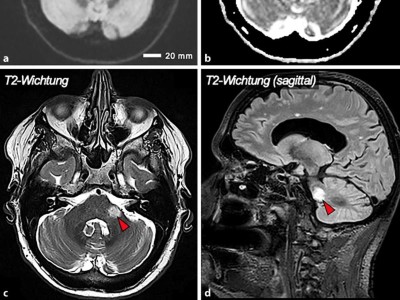

Seit zwei Tagen verspürt ein 66-Jähriger einen konstanten Drehschwindel mit linkseitiger Hörminderung. An einen Auslöser kann sich der Patient nicht erinnern. Der Patient weist ein Nystagmus auf und eine deutliche Rückstellsakkade bei Drehung nach links im Kopfimpulstest. Besteht hier ein Notfall?

Hinter akutem Drehschwindel kann sich eine relativ harmlose Ursache verstecken wie eine Neuritis vestibularis - aber auch ein Hirnstamm- oder ein Kleinhirninfarkt. Dreht es sich immer mal wieder, ist ein Morbus Menière oder eine vestibuläre Migräne möglich. Die systematische Anamnese und körperliche Untersuchung führen zur richtigen Diagnose und Therapie.

Bildnachweise